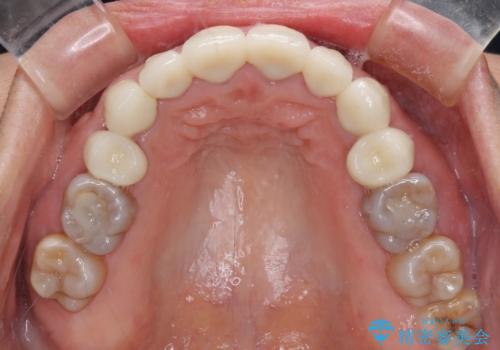

気になる変色歯を仮歯に変え、その後歯列不正を矯正治療で改善し、最後にオールセラミッククラウンにて補綴治療することとしました。

数十年に及んだ歯の変色が改善されたため、大変満足していただきました。